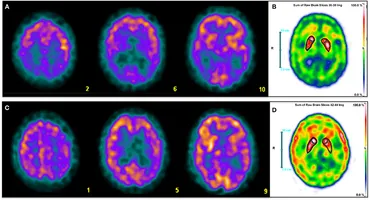

Diagnostic Imaging: Brain, 4th ed.: 洋書/南江堂。A Visual Interpretation Algorithm for Assessing Brain。Neuroimaging Biomarkers in Alzheimer's Disease and Related。eBook使用済みです。書籍としての状態は良好です。Covering the entire spectrum of this fast-changing field, Diagnostic Imaging: Brain, fourth edition, is an invaluable resource for neuroradiologists, general radiologists, and trainees-anyone who requires an easily accessible, highly visual reference on today's neuroimaging of both common and rare conditions. World-renowned authorities provide updated information on more than 300 diagnoses, all lavishly illustrated, delineated, and referenced, making this edition a useful learning tool as well as a handy reference for daily practice.Provides authoritative, comprehensive guidance on both pathology-based and anatomy-based diagnoses to help you diagnose the full range of brain and CNS conditionsFeatures thousands of extensively annotated images, including a large number of full-color illustrations-greatly expanded since the previous edition.#brain #神経 #神経解剖 #神経内科 #脳神経内科 #脳外科 #脳神経外科#脳 #脳解剖 #頭部画像 #頭部解剖 #MRI #頭部MRI #神経画像。Neuroimaging: CT Scan and MRI | SpringerLink。外傷形成外科 そのときあなたは対応できるか